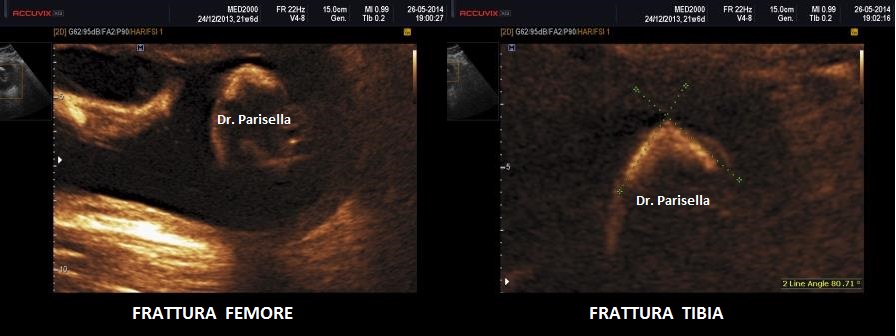

c.Fratture

I quattro arti devono essere studiati anche dal punto di vista qualitativo, oltre che biometrico, valutando la presenza o l'assenza di mineralizzazione, curvature, fratture, slargamento delle metafisi.

Le displasie caratterizzate da ipomineralizzazione, specie se spiccata, possono presentare fratture dei segmenti ossei interessati.

Un altro dato da valutare è il grado di curvatura ossea; le due principali condizioni che possono presentare in epoca prenatale un incurvamento delle ossa lunghe sono l'osteogenesi imperfetta e la displasia tanatofora tipo I (femori a cornetta di telefono).